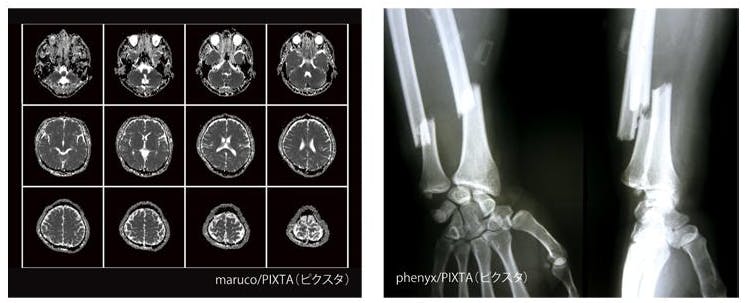

迷你「X光燈箱」尺寸約為 39 mm × 49 mm × 17 mm,內建發光功能,只要打開開關,便能亮起內部光源。產品還附有迷你版的X光片,可以讓使用者體驗一下醫療人員般的感覺。背面內建磁鐵,可以吸附在冰箱或置物櫃等地方作為裝飾。除了觀賞附屬的迷你X光片,使用者也可將手上的底片放在上面,滿足自以為是神醫的樂趣(?),搭配模型、公仔、玩偶更促咪。

售價400日圓,共有5款造型可供收集,這裡看更多。